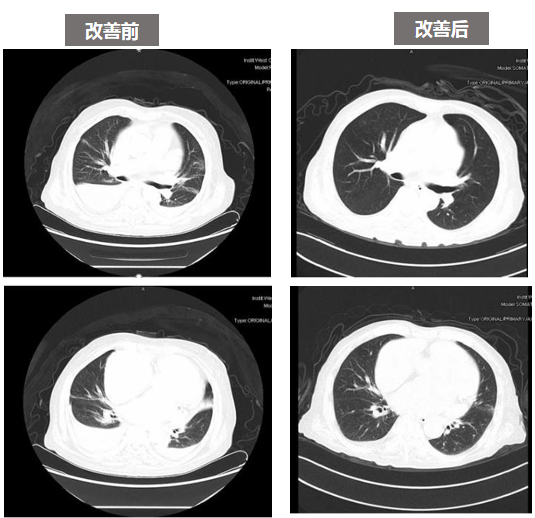

胸部 CT:

患者治疗后复查胸部 CT 提示炎症大部分吸收,胸水明显减少,患者一般状况好,无明显不适症状。